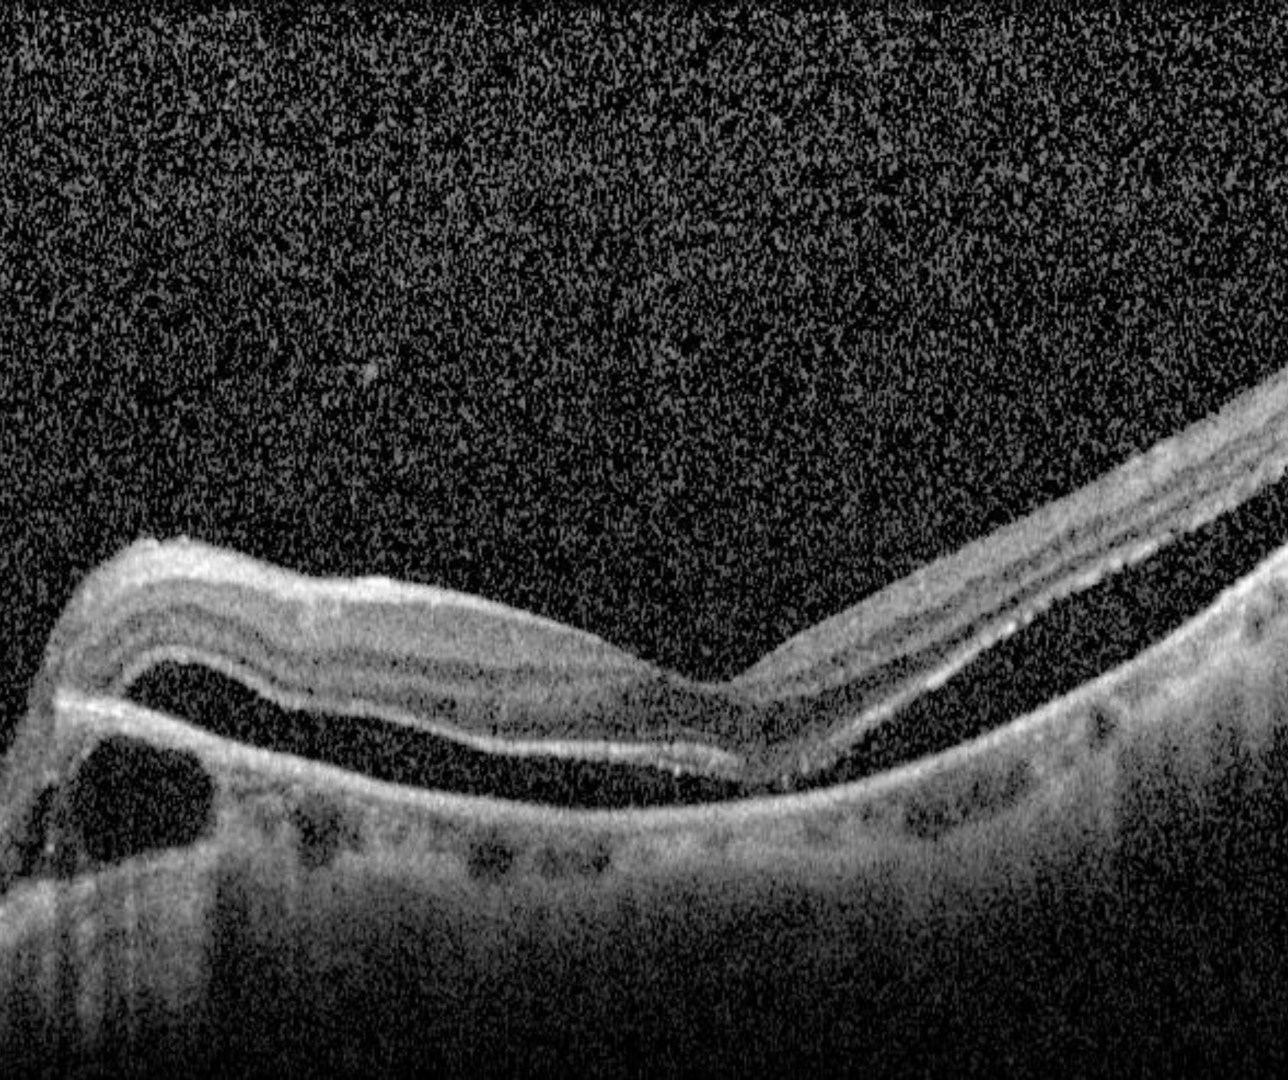

Case 2: Foveal detachment

A 59 year old Asian male with refraction -9.75 / -2.00 x 70 and visual acuity 6/12 (20/40).

The term foveal detachment refers to a separation of the neurosensory retina from the RPE at the fovea.